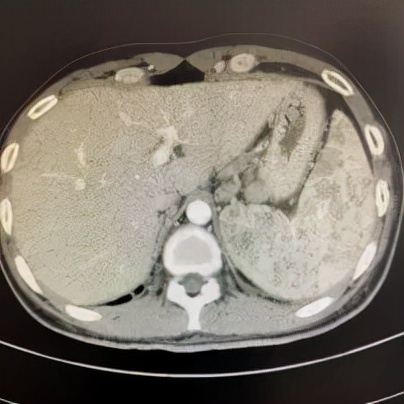

腹部CT腹膜后淋巴结肿大,脾脏多发结节病变(图3)。

图3:腹部CT示脾脏多发结节病变